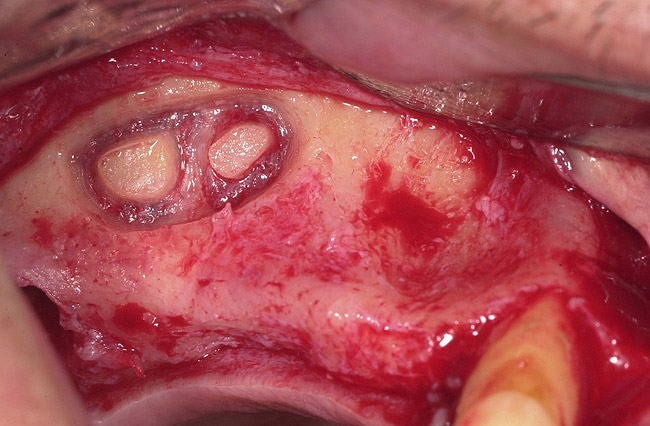

Management of Sinus Septa

The incidence of sinus septum is 24% to 41%, with high variability in size and location; identification of the septum before the surgical sinus lift will reduce the possibility of complications.3,4 The location of the septum will dictate the size and design of the lateral wall osteotomy. The septum is isolated through careful lateral window osteotomy, defining two compartments mesial and distal to the septum. Figure 22, Figure 23, Figure 24, Figure 25 and Figure 26 illustrate proper management of the septum.

Figure 22  Sinus septum evident at site No. 3.

Figure 22

Figure 23  First, the sinus septum was identified.

Figure 23

Figure 24  Then, the septum was isolated.

Figure 24

Figure 25  Lastly, the septum was managed.

Figure 25

Figure 26  Bong graft was placed in the mesial and distal compartments.

Figure 26